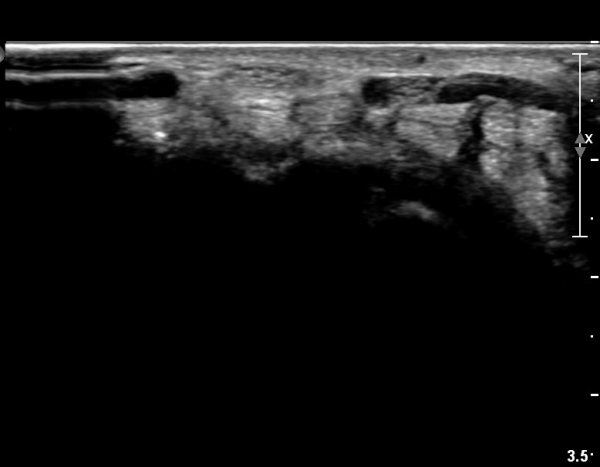

ÃÊÀ½ÆÄ ¼Ò°ß :  ¼Õ¸ñ±ÙÀ§ºÎ Ⱦ´Ü¸é°Ë»ç¿¡¼­ ¼Õ¸ñ±¼±Ù°Ç(FCR)°ú Ç¥Ãþ ¼Õ°¡¶ô ±ÁÈû±Ù(FDS) »çÀÌ¿¡

Á¤Á߽ŰæÀÌ Á¤»óÀûÀÎ ¾ç»óÀ¸·Î º¸ÀÓ(»çÁø 1).

Å½ÃËÀÚ¸¦ ¸»´ÜÀ¸·Î À̵¿ÇÏÀÚ  Á¤Áß½Å굥 ¿äÃø ÀϺΰ¡ Àú¿¡ÄÚ Á¾±«·Î °üÂûµÊ(»çÁø 2).